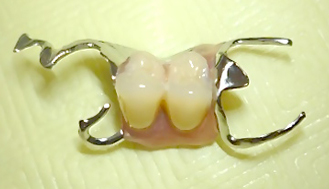

失った前歯2本の根は割れていたため、残せそうにありません。しかし、このままでは見た目が良くありませんので、割れた根の上から入れ歯を乗せて、急いで前歯を復元させることにしました。型取りをしてから10日後、部分入れ歯=写真上=の完成です。 続きを読む